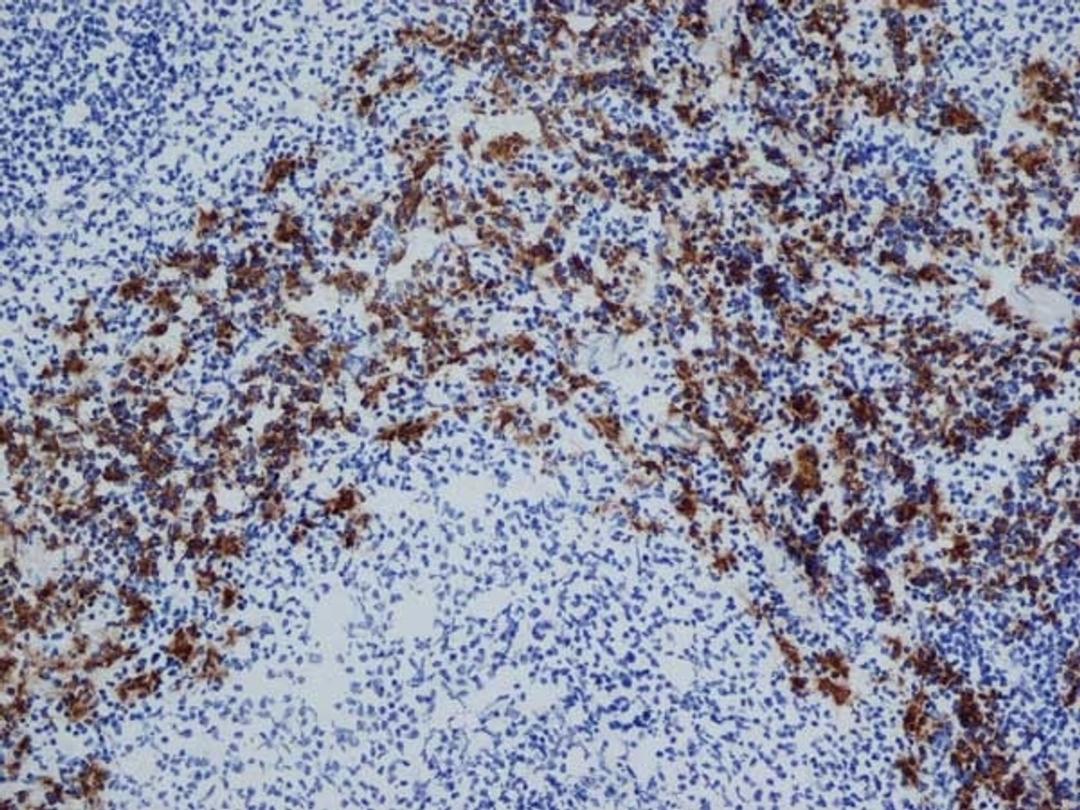

CD163

MOUSE ANTI RAT CD163

- Immunohistochemistry (Frozen Sections) (IHC (Fr))

- Immunohistochemistry (Paraffin-Embedded Sections) (IHC (P))